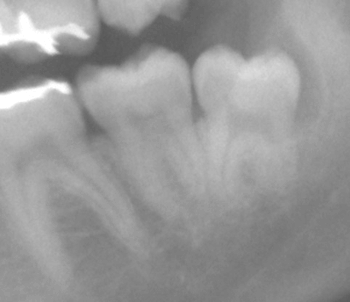

右端が親知らずです! 比較的真っ直ぐだけど、根が2本???

先が曲がって「C」みたいになってますが、親知らずは根が短く簡単に抜ける事も多いので、最悪は分割して時間をかければ抜けますよ! と安易な説明で開始、 |